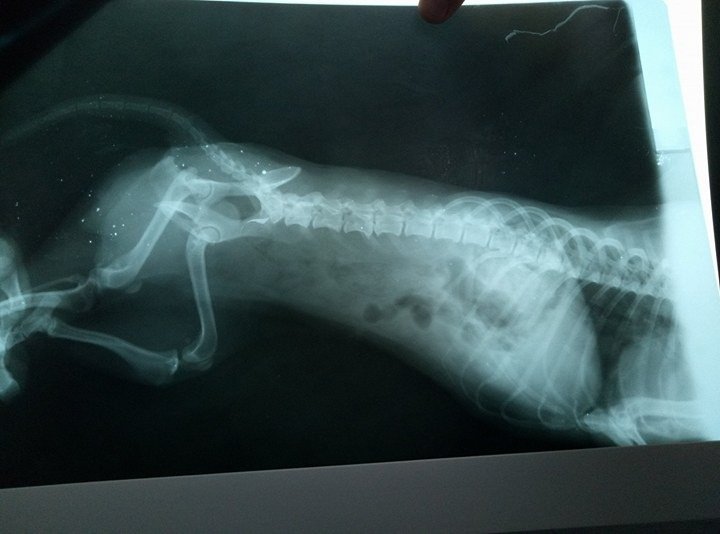

Оказалось, что собачка совсем молоденькая, и у нее очень серьезные проблемы со здоровьем. «Позвоночник весь болит. Невозможно дотронуться, она скулит, дергается и плачет. По рентгену переломов нет. Задними лапками не ходит. Немного встает на передние, но только чтобы перелечь поудобнее. Больше не двигается вообще», – говорит Юлия. Также анализы показали проблемы с сердцем и внутренними органами.